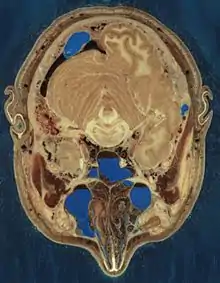

Cryosection through the head of a human male

The Visible Human Project is an effort to create a detailed data set of cross-sectional photographs of the human body, in order to facilitate anatomy visualization applications. It is used as a tool for the progression of medical findings, in which these findings link anatomy to its audiences.[1] A male and a female cadaver were cut into thin slices, which were then photographed and digitized. The project is run by the U.S. National Library of Medicine (NLM) under the direction of Michael J. Ackerman. Planning began in 1986;[2] the data set of the male was completed in November 1994 and the one of the female in November 1995. The project can be viewed today at the NLM in Bethesda, Maryland.[3] There are currently efforts to repeat this project with higher resolution images but only with parts of the body instead of a cadaver.

The male cadaver was encased and frozen in a gelatin and water mixture in order to stabilize the specimen for cutting. The specimen was then "cut" in the axial plane at 1-millimeter intervals. Each of the resulting 1,871 "slices" was photographed in both analog and digital, yielding 15 gigabytes of data. In 2000, the photos were rescanned at a higher resolution, yielding more than 65 gigabytes. The female cadaver was cut into slices at 0.33-millimeter intervals, resulting in some 40 gigabytes of data.

Freezing caused the brain of the man to be slightly swollen, and his middle ear ossicles were lost during preparation of the slices. Nerves are hard to make out since they have almost the same color as fat, but many have nevertheless been identified. Small blood vessels were collapsed by the freezing process. Tendons are difficult to cut cleanly, and they occasionally smear across the slice surfaces.